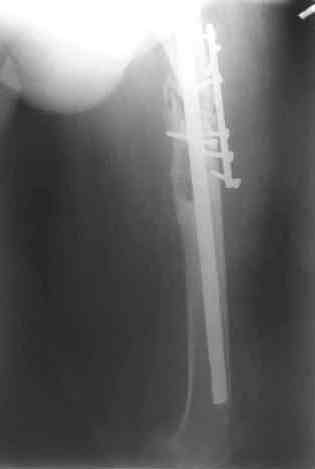

Этот стиль мне полностью приемлем и понятен. Наверно я бы поступил также. Но статистика упрямая вещь. Сколько у тебя или у другого врача опыта по замещению дефектов бедра? У меня за 25 лет работы 3, и еще около 15 случаев удлинения бедра. Случай у тебя очень сложный. Если Вы выбираете Илизаровскую методику то надо на в/з хорошую дугу, не менее 4-5 спиц с напайками.Стержни хороши когда кость не измучена и на 2-4 месяца. Здесь аппарат на 6-8 месяцев. Если есть желание я только за, и

желаю только успеха и чтоб все трудности которые будут преодолел.

Прикрепляю пример замещения дефекта бедра 20 см, после резекции по поводу опухоли, эндопротеза Сиваша, вялотекущего остеомиелита со свищами в течении 3 лет. Получилось хорошо и всего за 6 месяцев в аппарате. Колена не было. У Вас случай сложнее. Это было в 1998г. Я работал в ЦИТО и у меня было 4 больных, я занимался им с утра до ночи. Сейчас 60 больных и операций в нашем отделении 25-30 в неделю.Если могу чем помочь - нет проблем.